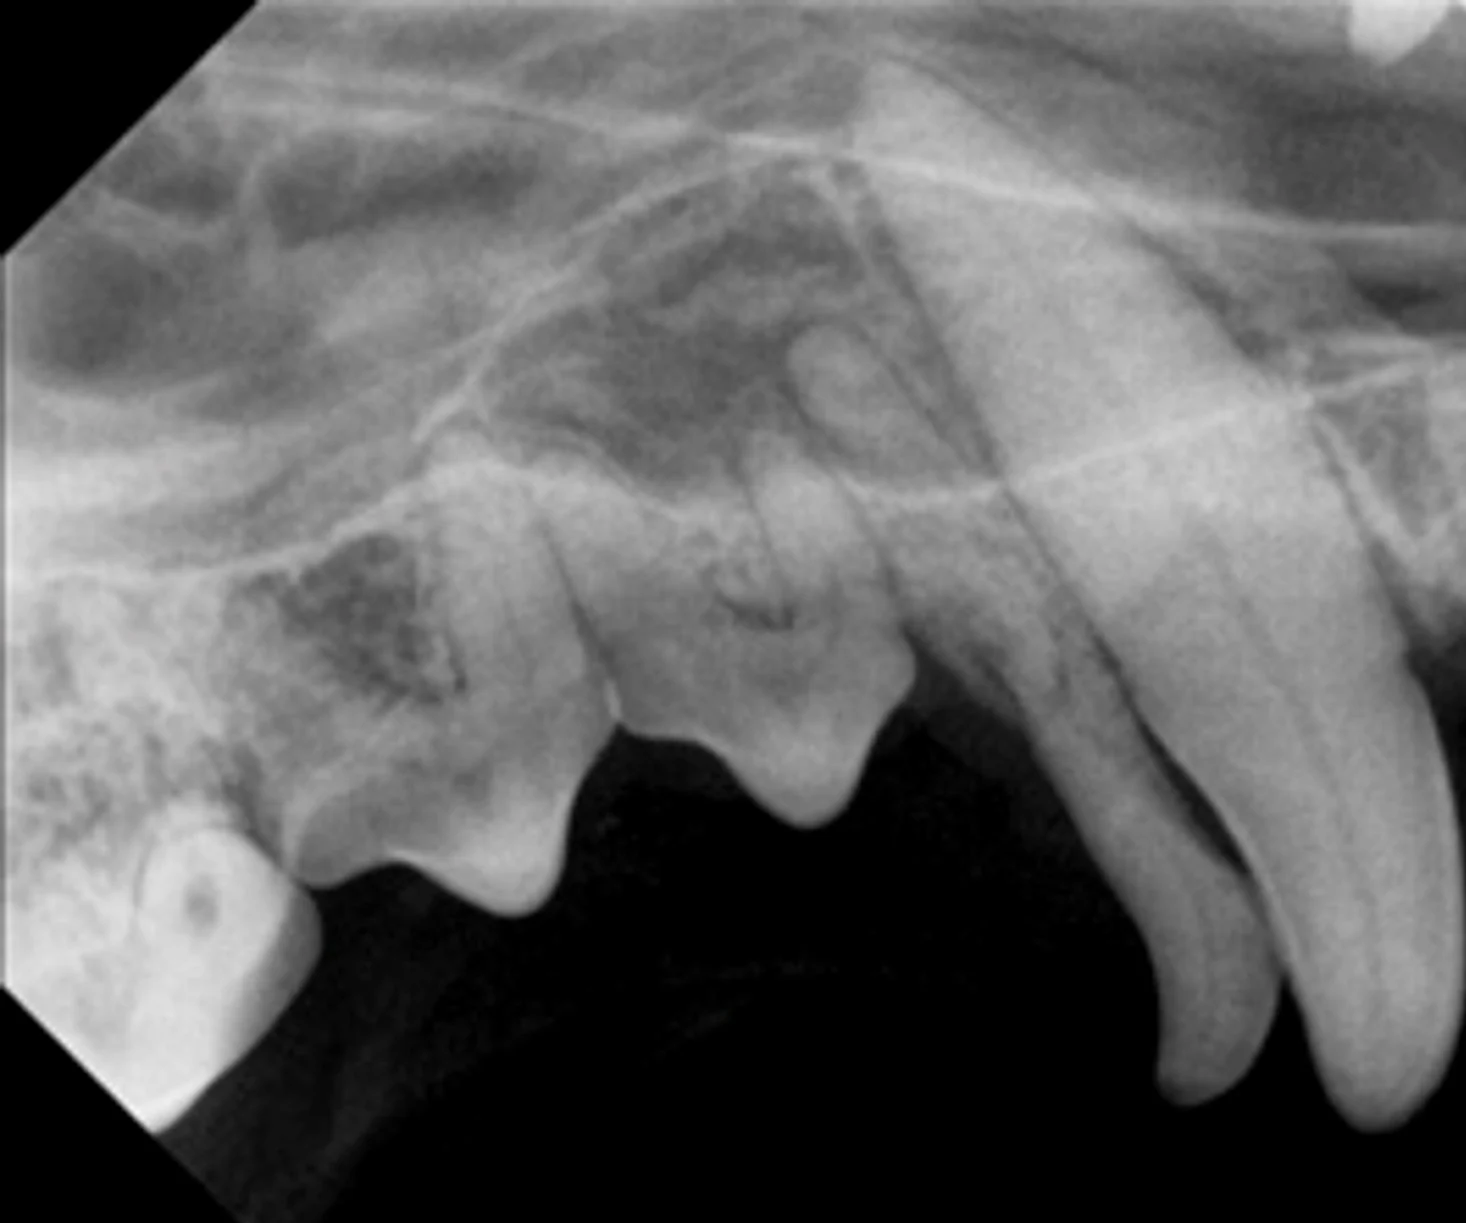

Think you can catch what’s hiding in these dental images? Sink your teeth into the quiz and see how you score.